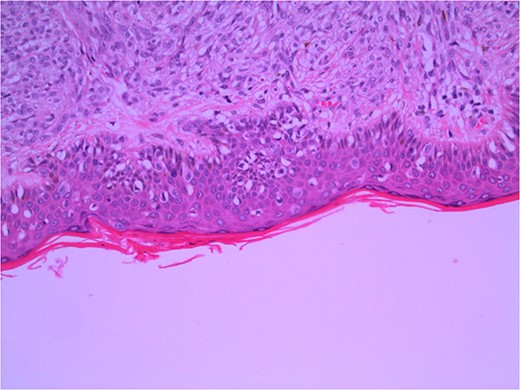

Excisional biopsy of the primary lesion was performed by his general practitioner which confirmed the diagnosis of Lentigo Maligna melanoma. Breslow thickness was 1.9 mm, and the deep margin demonstrated an invasive component to 2 mm, equating to Clark 4 invasion. Junctional melanocytes showed moderate to marked atypia, with sheets of melanocytes in the dermis (Fig. 1). There was no ulceration or lymphovascular invasion. This was followed by wide local re-excision. Adjacent epidermis showed a mild increase in atypical melanocytes, with no contiguous proliferation. No residual in situ or invasive malignancy was detected. He underwent a staging computed tomography (CT) that did not identify distant metastases.

Wide local excision of primary lesion demonstrating pagetoid spread in epidermis and infiltration into reticular dermis; H&E × 200 magnification.